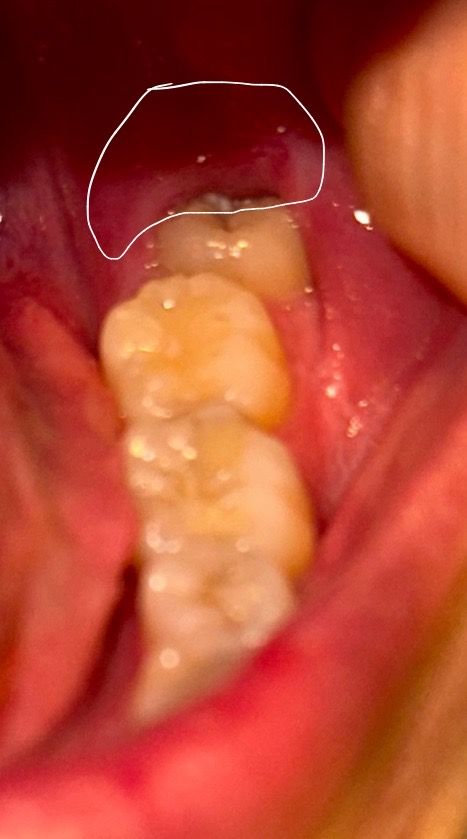

갑자기 잇몸쪽이 아픈데 이거 매복 사랑니인가요??..

6년전쯤 아래 사랑니 한쪽 뽑았는데 어딘지 기억이 안나네요.. 치아 갯수 세어보니…왼쪽이 하나 더 있는데..이게 사랑니인가여 ㅠㅠ 잇몸 완전 안쪽에 치아가 살짝 파여있는치아가 있는데 이게 사랑니인지 뭔지 모르겟네요..

• 1번 째 사진

해당 치아는 부분 매복된 사랑니가 맞으며 불편감이 지속될 시에는 발치를 하시는 게 좋습니다.

사진상으로 보면 사랑니가 맞는거 같습니다 사랑니 부위에 염증이 심한거 같으니 치과에 가셔서 잇몸치료 또는 발치를 하시는게 좋을것같습니다.

사진으로 봤을 때 해당 치아는 사랑니로 보입니다. 사랑니로 인해서 잇몸에 불편감이 있고 염증이 생긴다면 사랑니를 발치해주는 것이 좋을 수 있습니다. 자세한 확인을 위해서 치과에서 진료를 받아보는 것을 권유드립니다.

1. 부분 매복 사랑니입니다.

2. 부분매복 사랑니가 잇몸을 자극해서 그렇고요. 사진상 봤을때 충치도 있어 보입니다.

3. 치과에서 사랑니 발치에 대해 의논해보시기 바랍니다.

6년 전에 사랑니를 한쪽만 뽑았다면 반대쪽 사랑니가 남아있을 가능성이 있습니다. 치아가 부분적으로만 드러나 있거나 파여 있는 경우 사랑니일 가능성이 높습니다.

현재 치아가 잇몸 속에 묻혀 있거나 불편함이 있는 경우 치과에서 엑스레이 촬영을 하고, 검사를 받고 발치 필요여부를 확인후 조치를 취하길 권합니다.